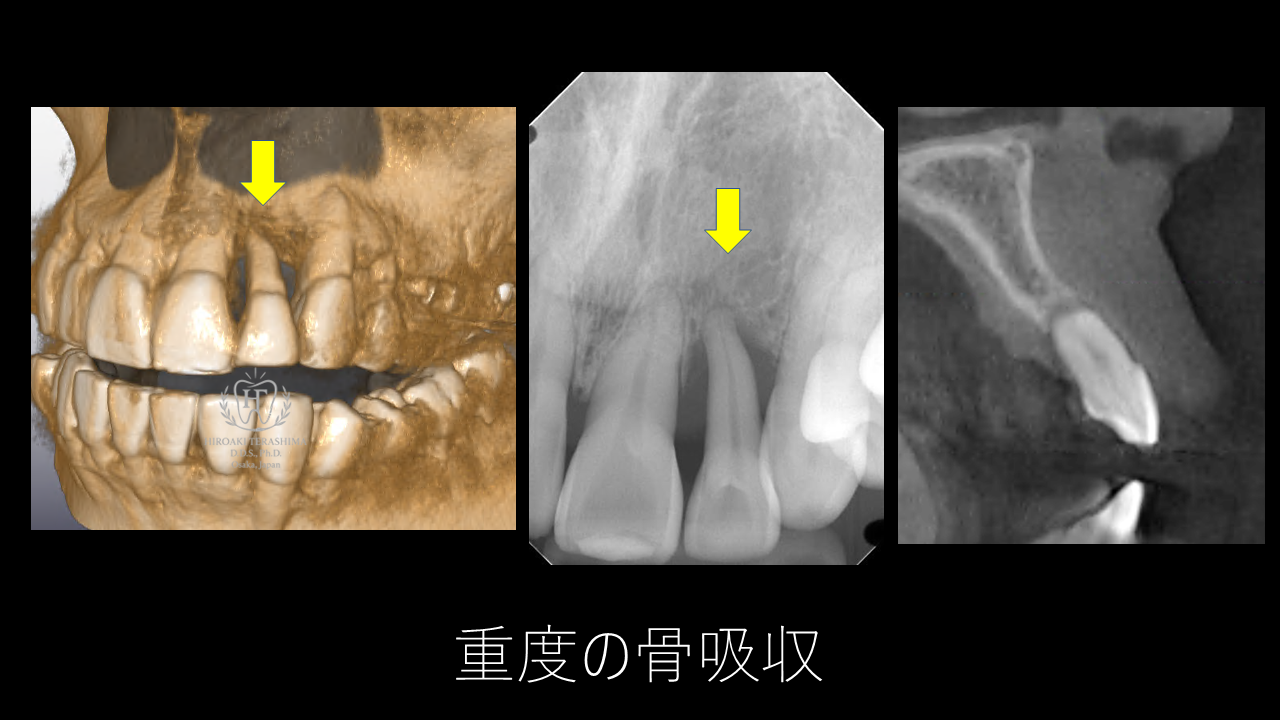

左上2番は重度歯周炎による骨吸収が根尖まで進行し、歯がぐらぐらしていました。隣の歯と接着剤で固定されていましたが、歯肉退縮と歯肉の厚み不足がすでに顕著で、非常に難易度の高い症例でした。

CTとレントゲンで確認すると、根尖まで骨が溶けており保存は困難。抜歯即時埋入インプラントを計画しました。![]()